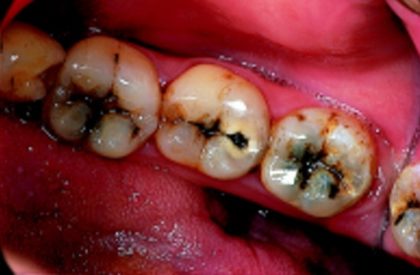

DENTAL CARIES:

It occurs when bacteria feed on the food particles that are stuck in tooth crevices. These food particles act as foci where cariogenic bacteria colonize. The demineralized area is less resistant and harbors an increased number of bacteria as compared to a normal structure. And over a period of time, there develops a cavity which is not going to revert back into the normal structure.

Initially, dental caries can be treated by simple restoration but if left untreated to, it may eventually require more aggressive and invasive treatment such as RCT or even EXTRACTION.